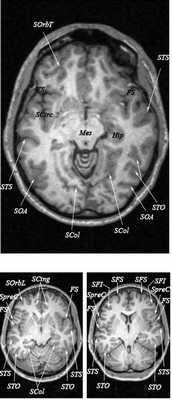

Анатомия головного мозга в МРТ изображении

МРТ головного мозга. Т2-взвешенная аксиальная МРТ. Цветовая обработка изображения.

Знание анатомии мозга очень важно для правильной локализации патологических процессов. Ещё более важно оно для изучения самого мозга с помощью современных «функциональных» методов, таких как функциональная магнитно-резонансная томография (fMRI), и позитронно-эмиссионная томография. С анатомией мозга мы знакомимся ещё со студенческой скамьи и существует множество анатомических атласов, в том числе и поперечных сечений. Казалось бы, зачем ещё один? На самом деле, сравнение МРТ срезов с анатомическими приводит к множеству ошибок. Это связано как со специфическими особенностями получения МРТ изображений, так и с тем, что строение мозга очень индивидуально.

Представленная страница сайта основана на специальном изучении МРТ головного мозга здоровых лиц. Для этого изображения получали с минимальной величиной воксела (1 мм в каждом измерении), что исключало наслоения борозд. Каждая из структур прослеживалась в трёх реконструированных плоскостях путём её выделения с помощью компьютерной программы. Мы рассматривали различные анатомические варианты, что обсуждается в работе. В результате, учитывая вариабельность строения мозга, подобран условно «стандартный» мозг. Поскольку на сайте нереально представить 128 срезов в каждой из основных плоскостей, мы ограничились только каждым пятым срезом. Основные срезы в поперечной плоскости даны без наклона назад (угол 0º). Под ними для представления о изменении соотношения анатомических структур демонстрируются срезы, выполненные на тех же уровнях, но с наклонами назад -15º и -30º.

Список сокращений

Борозды

Междолевые и срединные

SC - центральная борозда

FS - Сильвиева щель (латеральная борозда)

FSasc - восходящая ветвь Сильвиевой щели

FShor - поперечная борозда Сильвиевой щели

SPO - теменно-затылочная борозда

STO - височно-затылочная борозда

SCasc - восходящая ветвь поясной борозды

SsubP - подтеменная борозда

SCing - поясная борозда

SCirc - круговая борозда (островка)

SpreC - предцентральная борозда

SparaC - околоцентральная борозда

SFS - верхняя лобная борозда

FFM - лобно-краевая щель

SOrbL - латеральная глазничная борозда

SOrbT - поперечная глазничная борозда

SOrbM - медиальная глазничная борозда

SsOrb - подглазничная борозда

SCM - мозолисто-краевая борозда

SpostC - постцентральная борозда

SIP - внутритеменная борозда

STS - верхняя височная борозда

STT - поперечная височная борозда

SCirc - круговая борозда

SCalc - шпорная борозда

SOL - латеральная затылочная борозда

SOT - поперечная затылочная борозда

SOA - передняя затылочная борозда

Поперечные (аксиальные) МРТ срезы головного мозга